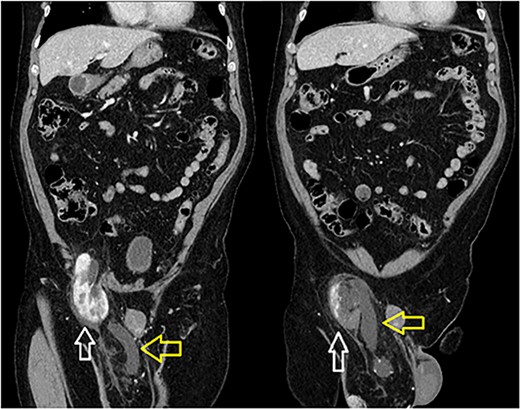

A 66-year-old Hispanic male presented to our emergency department with 1 week of right groin pain and swelling. He came to the hospital due to worsening pain. He denied any nausea, emesis or fever. He was passing gas and having bowel movements without difficulty. He denied any issues with voiding, hematuria or urinary urgency. His past medical history includes congenital deformity of his left upper extremity and past surgical history of open left inguinal hernia repair. His BMI is 32.5. His serum creatinine was 1.40 mg/dL. He had a normal white blood cell count at 9.8 × 103/UL and hemoglobin at 14.1G/DL. On examination, he had right inguinal tenderness to palpation with an obvious hernia extending to the scrotum. No skin changes were present. We were unable to reduce the hernia at bedside due to pain. A computed tomography (CT) of abdomen and pelvis with IV contrast showed herniation of the right kidney in the right inguinal hernia with the upper pole in the inguinal canal. The right renal artery and vein arose from the aorta and inferior vena cava, respectively, around the level of L1-L2 region (Fig. 1). The right ureter was incarcerated within the hernia and dilated up to 2 cm in diameter. The ureter transitions to normal caliber as it exits the hernia, concerning for obstructive uropathy (Fig. 2).

Incarcerated right kidney (white) in the inguinal hernia with distended ureter within the hernia sac (yellow).